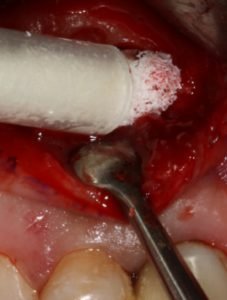

Figura 2: Osteogen® sendo enxertado com a seringa aplicadora;

O Osteogen® é uma hidroxiapatita sintética absorvível que atende a estes critérios descritos acima(1, 4, 5).

Outra grande vantagem deste material é a sua apresentação clínica que vem com uma seringa aplicadora que facilita muito a sua manipulação independente do sistema do uso de soro, sangue ou fatores de crescimento para sua aglutinação.